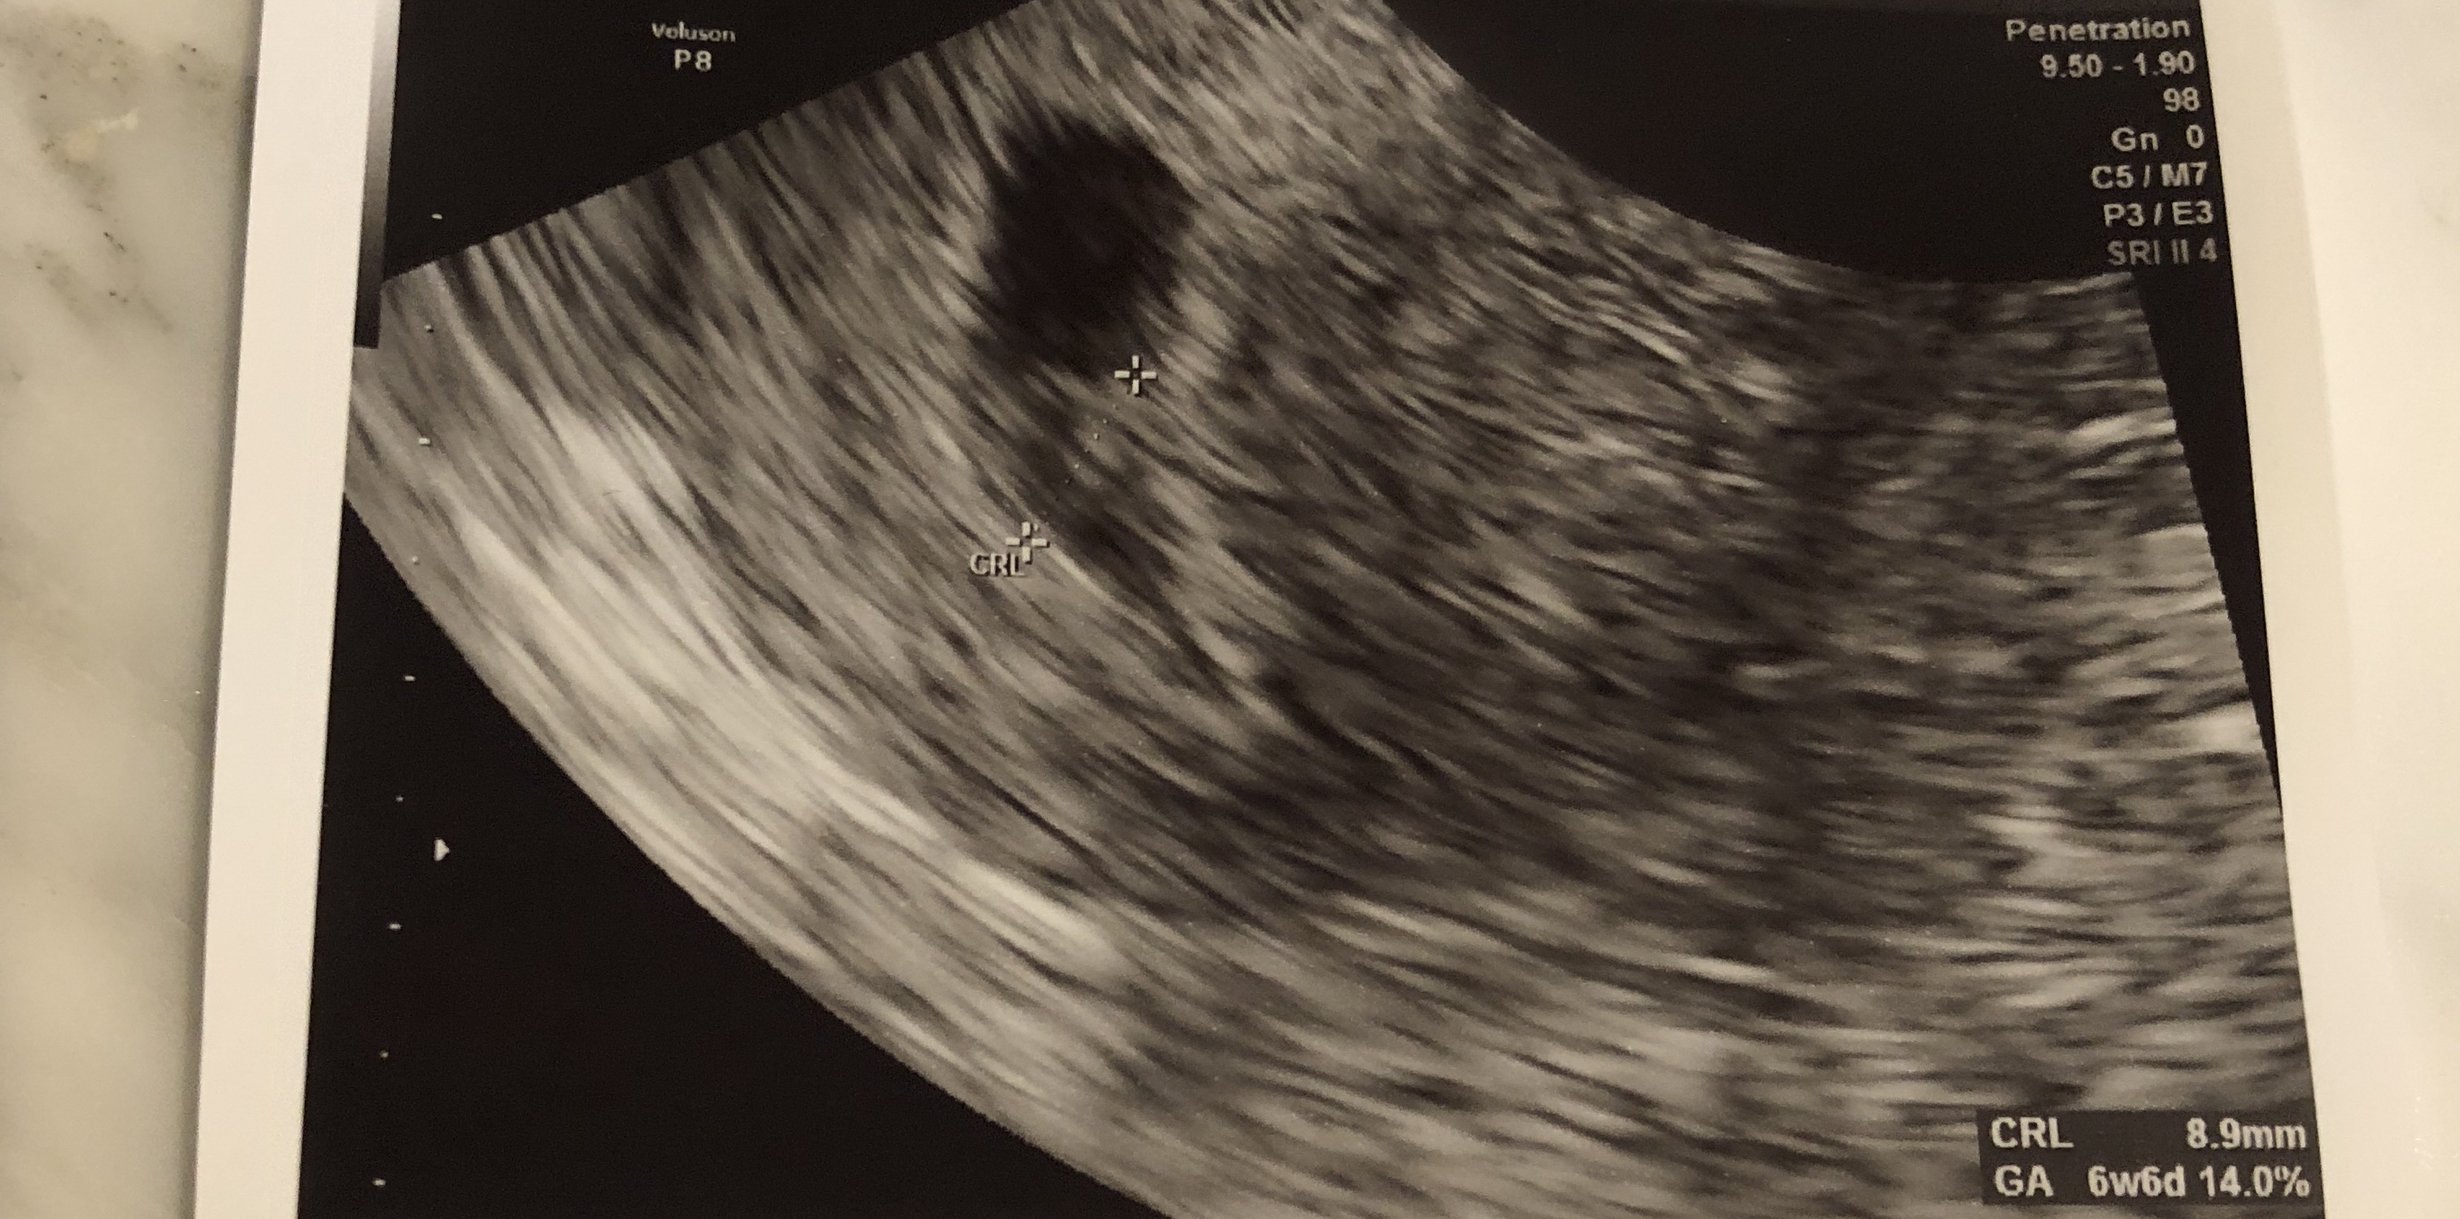

Hi everyone, 6 weeks ultrasound. I’m scheduled back for an 8 weeks ultrasound. Doctor said it’s twins but one is smaller than the other one that we had to wait and see if the other progresses. Has anyone had a similar situation? This is my 3rd pregnancy but first time twins.

• I had my first ultrasound on Monday! I'm not as far along as I thought - I thought I was past 10 weeks but I'll be just 10 weeks tomorrow. So glad I decided to have an early ultrasound - last pregnancy I just had one at 20 weeks. This time around I was having cramping and bleeding and something seemed off. I guess this is why!!!! Seeing double!! They think identical but can't quite be certain yet as I only wanted an abdominal ultrasound this visit. Needless to say I'm freaking out! New due date of November 8th instead of the 3rd...but I'm sure with twins it may be October!